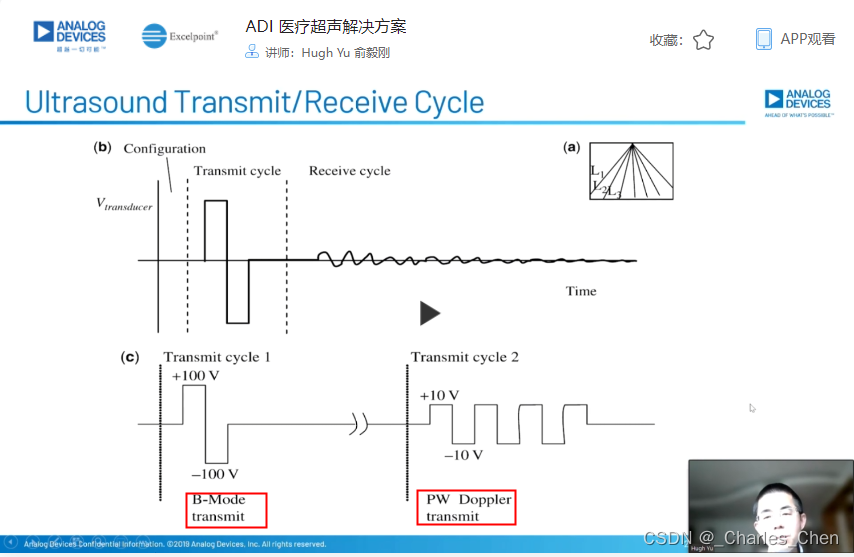

通过发射超声能量进入人体,接收并处理返回的反射信号,相控阵超声系统可以生成体内器官和结构的图像,映射血液流动和组织运动,同时提供高准确度的血流速度信息。传统设计中,构建这样的成像系统需要大量的高性能相控阵发射器和接收器,使得车载设备体积庞大且价格昂贵。近年来,随着集成工艺的进步,设计人员能够获得小尺寸、低成本而且高度便携的成像系统方案,并可达到接近大型成像设备的性能指标。而新的设计挑战依然存在,即在进一步提高方案集成度的同时提高系统性能和诊断能力。

成像系统的关键器件是超声传感器。典型的超声成像系统需要使用各种传感器支持特定的诊断要求。每个传感器由一组压电传感器单元阵列构成,它们集中能量并发射到人体内部,然后接收相应的反射信号。每个单元通过纤细的同轴电缆连接到超声系统。通常,传感器由32至512个单元构成,工作频率为1MHz至15MHz。多数超声系统提供两个至四个传感器转换接口,临床医生可根据不同的检测类型方便地更换传感器。

高压复用开关

典型的相控阵超声系统配备了32至256个发射器和接收器。多数情况下,系统配备的发射器和接收器的数量少于传感器单元的数量。这些情况下,需要在传感器或系统中安装高压开关,用于信号复用,开关连接在特定的传感器单元和发送器/接收器(Tx/Rx)对之间。由此,系统能够在所提供的传感器阵列中动态改变有效的传感器孔径。

数字发射波束成形器用于产生所要求的数字发射信号,以正确的时间和相位生成聚焦发射信号。高性能超声系统可通过任意波形发生器产生复杂的发射波形,从而优化图像质量。这些情况下,发射波束成形器以大约40MHz速率生成8位至10位数字字符,并以此产生所要求的发射波形。数/模转换器(DAC)将数字波形转换成模拟信号,通过线性高压放大器进行放大,用于驱动传感器单元。由于这种发射技术占用较大体积,而且价格昂贵、需要消耗较高能量,所以,这种架构只限于昂贵的非便携设备。多数超声系统并不使用这种发射波束成形技术,而是采用多级高压脉冲发生器产生需要发射的信号。在这种替代方案中,利用高集成度、高压脉冲发生器快速切换传感器单元至适当的可编程高压电源,产生发射波形。为了产生一个简单的两极发射波形,脉冲发生器需要交替地将传感器单元切换到由数字波束成形器控制的正、负发射电压。更复杂的设计可以让传感器单元切换至多路电源和地,从而产生更复杂、性能更好的多重波形。